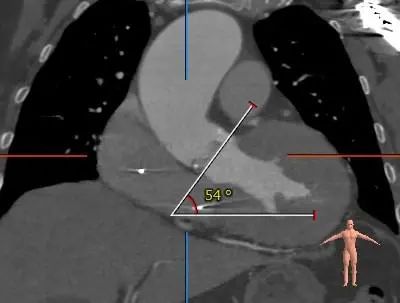

2021年12月4日,郑州市第七人民医院赵育洁主任、张申伟主任团队成功完成TaurusElite®可回收经导管主动脉瓣系统首例植入。此病例十分典型,Type 0型二叶式主动脉瓣,重度钙化主要沿两窦瓣叶边缘连续分布,瓣叶增厚,窦内少量钙化向窦底延伸至瓣环水平,瓣环水平夹角54接近横位心,升主动脉严重扭曲。术后瓣膜工作正常稳定,未出现冠脉阻挡和瓣周漏等情况,血流动力学均得到有效改善,为患者带来更长久生存期受益和更高生活质量。

1.Type 0 型二叶瓣,瓣叶增厚,双侧瓣叶边缘连续条状钙化,瓣膜锚定难度适中,瓣膜植入受两侧钙化挤压存在移位风险及瓣周漏风险。

3.接近横位心,升主动脉扭曲,弓顶部角度略锐,宽度适宜,预计输送器可顺利过弓,输送器跨瓣难度增高,必要时Snare辅助。

2.接近横位心,升主动脉严重扩张并扭曲,跨瓣、球囊及输送器跨瓣难度增高